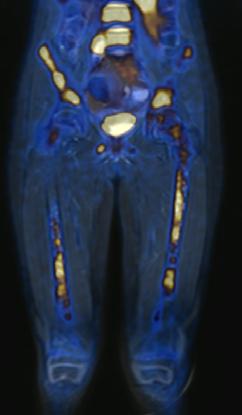

Figura 1A) Estudio PET con 6-[18F]FDOPA positivo para actividad tumoral del primario conocido en abdomen y retroperitoneo, con metástasis difusas en la médula ósea del esqueleto axial y apendicular.

Figura 1B) Estudio PET con [18F]OCTREOTIDE con sobreexpresión anormal de los receptores de somatostatina en retroperitoneo y esqueleto axial y apendicular.

Al correlacionar con 6-[18F]DOPA (Figura 1A) se observa que las lesiones tienen mayor sobreexpresión de los receptores de somatostatina.

Femenino de 7 años con diagnóstico de Neuroblastoma, se realiza PET/RM con [18F]F-DOPA para estadiaje, con evidencia de lesión primaria a nivel de retroperitoneo y conglomerados locoregionales así como infiltración a médula ósea del esqueleto axial y apendicular (Figura 1A), posteriormente la paciente fue tratada quirúrgicamente con resección de la lesión primaria así como tratamiento con inmunoterapia y transplante autólogo de médula ósea además de radioterapia. Al presentar refractariedad al tratamiento comentado, se plantea la posibilidad de administrar Lutecio (177Lu) oxodotreotide, por lo que se sugiere realizar PET/RM con [18F]Octreotide para valorar expresión de receptores de somatostatina y considerar la terapia con radionúclidos para receptores de péptidos (PRRT), el estudio muestra evidencia de sobreexpresión anormal de dichos receptores en retroperitoneo, espacio subpleural izquierdo además de esqueleto axial y apendicular (Figura 1B).

Estudio PET con 6-[18F]DOPA 3A) y [18F]OCTREOTIDE 3B) en cortes coronales de secuencias T2 de miembros pélvicos y con imágenes fusionadas, donde se identifica mayor sobreexpresión anormal de los receptores de somatostatina al compararlos con 6-[18F]DOPA, y que hace candidata a la paciente para PRRT.